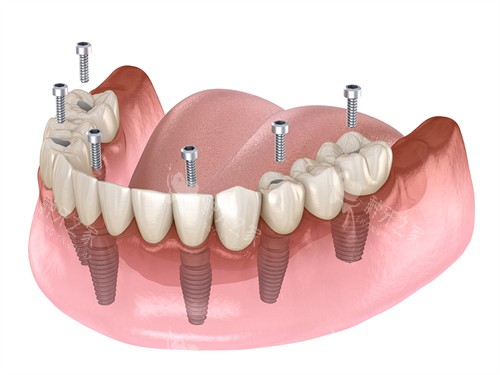

做半口或全口种植牙6年后,使用者普遍收获了咀嚼功能重塑、口腔状态稳定、生活质量提升的正向体验。不同修复技术、不同年龄段的网友,均反...